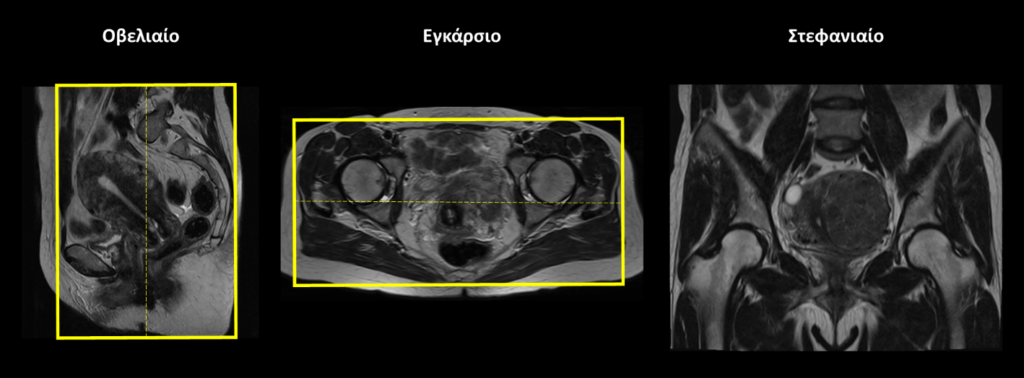

Εγκάρσιο επίπεδο (Axial/Transversal): Σχεδιάζουμε το εγκάρσιο επίπεδο χρησιμοποιώντας τις εικόνες που βρίσκονται σε οβελιαίο και στεφανιαίο προσανατολισμό. Οι εγκάρσιες τομές σχεδιάζονται κατά μήκος των οργάνων της κάτω κοιλίας τόσο στο στεφανιαίο όσο και στο οβελιαίο επίπεδο. Δεν απαιτείται ιδιαίτερη κλίση. Οι τομές πρέπει να περιλαμβάνουν ολόκληρη την κάτω κοιλία, από το διχασμό της αορτής (πάνω) μέχρι και την ηβική σύμφυση (κάτω). Μπορούμε να προσθέσουμε saturation bands μπροστά στην περιοχή του υποδόριου λίπους και πάνω από την περιοχή απεικόνισης (εκτός του FOV) προκειμένου να μειώσουμε τα artifacts κίνησης και ροής.

Στεφανιαίo επίπεδο (Coronal): Σχεδιάζουμε το στεφανιαίο επίπεδο χρησιμοποιώντας τις εικόνες που βρίσκονται σε οβελιαίο και εγκάρσιο προσανατολισμό. Οι στεφανιαίες τομές σχεδιάζονται στο εγκάρσιο επίπεδο παράλληλα με τις κεφαλές των μηριαίων. Ελέγχουμε στο εγκάρσιο και το οβελιαίο επίπεδο την περιοχή απεικόνισης που πρέπει να ξεκινά από τους ορθούς κοιλιακούς (μπροστά) μέχρι το ιερό οστό (πίσω). Μπορούμε να προσθέσουμε saturation band πάνω από την περιοχή απεικόνισης (εκτός του FOV) προκειμένου να μειώσουμε τα artifacts κίνησης και ροής.

Οβελιαίο επίπεδο (Sagittal): Σχεδιάζουμε το οβελιαίο επίπεδο χρησιμοποιώντας τις εικόνες που βρίσκονται σε εγκάρσιο και στεφανιαίο προσανατολισμό. Οι τομές σχεδιάζονται παράλληλα με την μήτρα και πρέπει να καλύπτουν τη μήτρα και τις ωοθήκες.